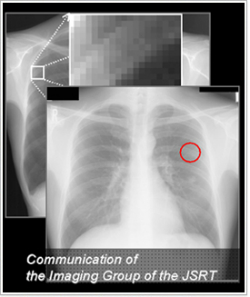

画像部会

画像部会は、医用画像の臨床評価及び画質評価、画像処理に関して興味を持つ約700名の会員により構成される日本放射線技術学会のサブグループです。画像部会では、医用画像の臨床評価に関する重要なテーマを、タイムリーに取り上げることを目指しており、医用画像に関する新しい技術や概念なども含めて、様々な情報を部会員に速やかに紹介し、その研究成果について議論を行なう場を積極的に提供しています。また、医用画像の臨床における有用性の評価法の普及のためのセミナーや、C言語プログラミングを含めたコンピュータ支援診断のセミナーも行っています。